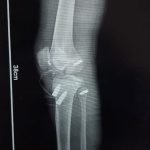

Orthopaedic Surgeon | Arthroscopy & Joint Replacement Specialist

Dr. Aditya Tripathi is a dedicated and skilled Orthopaedic Surgeon specializing in sports injuries, arthroscopy, and joint care. Known for his clinical precision, ethical practice, and patient-first approach, he focuses on helping patients regain mobility, strength, and confidence through evidence-based orthopaedic treatment. His academic background and hands-on clinical training reflect a strong foundation and a commitment to excellence in orthopaedic care.

Dr. Aditya Tripathi is widely appreciated by patients for his clear communication, honest medical guidance, and personalized treatment approach. His expertise in managing ACL tears, ligament injuries, shoulder conditions, and sports-related injuries makes him a trusted choice for comprehensive orthopaedic and sports injury care. Patients value his attention to detail, compassionate care, and focus on long-term recovery—establishing him as a reliable and respected orthopaedic specialist.

- Fracture Treatment